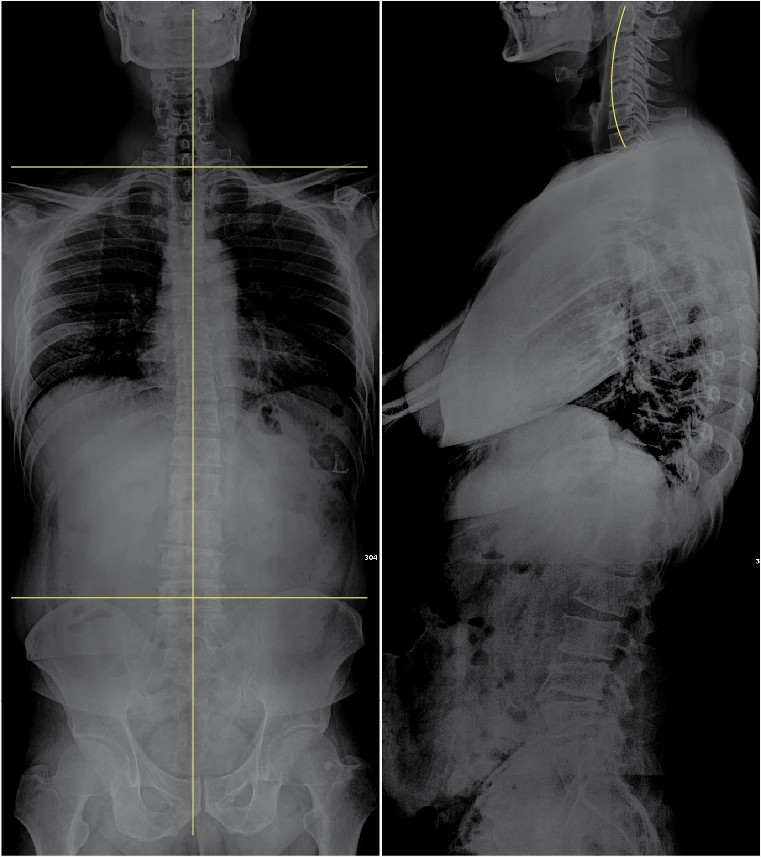

목.PNG

몸통.PNG

내 목은 일자목!

내 허리는 골반에서부터 틀어진 비정형 척추!

서프로는 내가 디스크라고 생각했던 허리를 골반 교정으로 바로잡았다. 거의 삼 개월 정도 된 지금 시점까지 오른쪽 발이 저리거나 한 적도 없었고 걷는 걸 두려워할 이유가 없어졌다. 이젠 다시 러닝을 시작해도 될 것 같다.